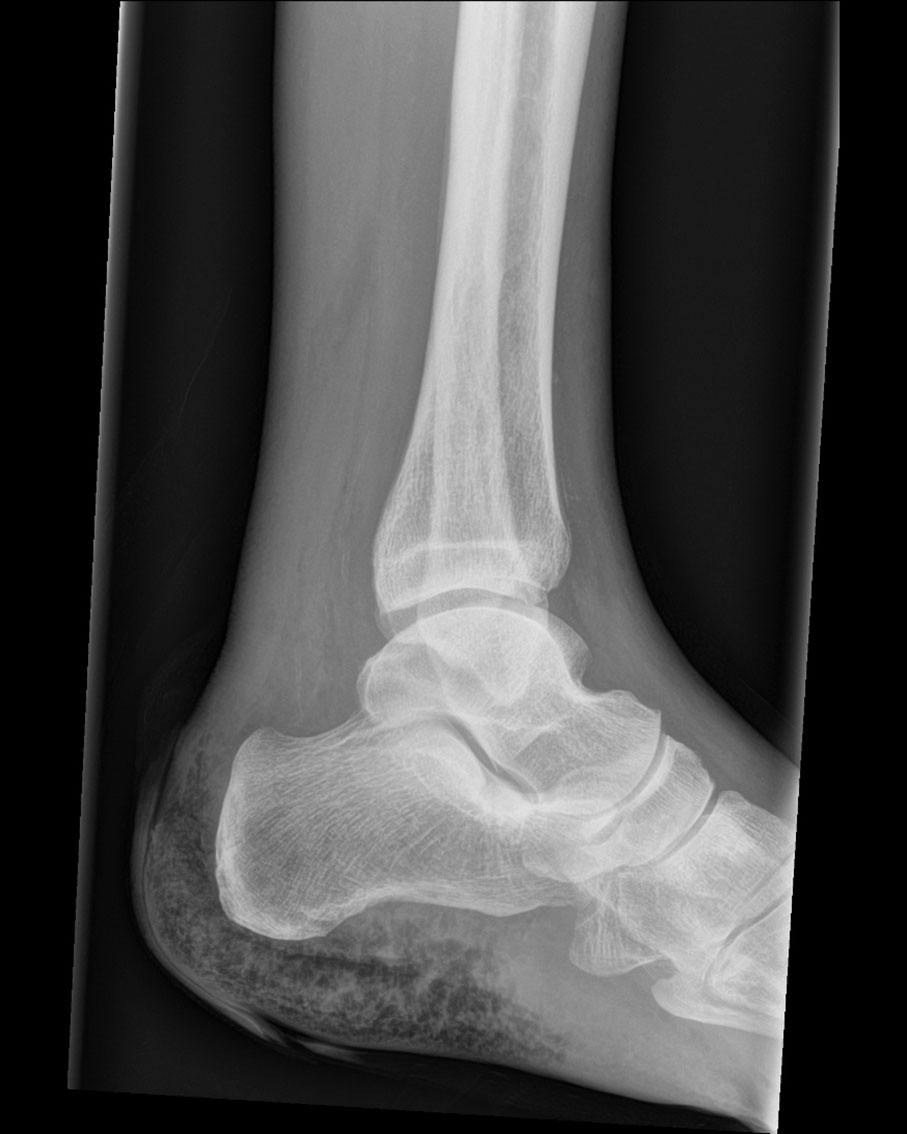

Dette røntgenbildet av venstre ankelledd viser gass i bløtvevet rundt hælen. Pasienten, en mann i 70-årene, ble innlagt i akuttmottak med feber og smerter i venstre fot. Han hadde kjent cancer coli med spredning til peritoneum og lunger. Fire år før den aktuelle innleggelsen hadde han gjennomgått høyresidig hemikolektomi, men avstått fra eventuell ytterligere kurativ behandling. Tre dager før innleggelsen utviklet han smerter i venstre ankel, og ble ifølge ektefellen forvirret og ytterligere redusert. Det forelå ingen opplysninger om traume, nylige sår eller utslett.

Dagen etter var det vekst av Clostridium septicum i to anaerobe blodkulturflasker. Samtidig tømte blemmen over hælen seg spontant med sterkt illeluktende væske. Det forelå ikke sikre palpable krepitasjoner. Røntgen av venstre ankelledd viste bløtvevsemfysem rundt hælen. Antibiotikabehandlingen ble endret til piperacillin-tazobaktam 4 g/0,5 g × 4 intravenøst. Halvannet døgn etter innleggelsen ble det på vital indikasjon utført giljotinamputasjon over malleolnivå i generell anestesi, og man igangsatte vakuumassistert sårbehandling. En uke senere ble det utført definitiv crusamputasjon med primær lukning av venstre underekstremitet. Etter ytterligere en ukes observasjon var det fredelige forhold over amputasjonsstumpen. Pasienten ble utskrevet til korttidsopphold i kommunen og henvist til rehabilitering for tilpasning av protese.